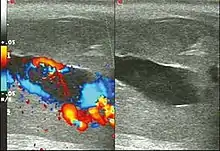

Color Doppler ultrasound demonstrating a hypoechoic collection that corresponds to hematoma with arteriovenous fistula secondary to traumatic injury of the penis due to impact with bicycle handlebars, resulting in high-flow priapism.[11]

Penile ultrasonography with doppler is the imaging method of choice, because it is noninvasive, widely available, and highly sensitive. By means of this method, it is possible to diagnose priapism and differentiate between its low- and high-flow forms.[11]

In low-flow (ischemic) priapism the flow in the cavernous arteries is reduced or absent. As the condition progresses, there is an increase in echogenicity of the corpora cavernosa, attributed to tissue edema. Eventually, changes in the echotexture of the corpora cavernosa can be observed due to the fibrotic transformation generated by tissue anoxia.[11]

In high-flow priapism normal or increased, turbulent blood flow in the cavernous arteries is seen. The area surrounding the fistula presents a hypoechoic, irregular lesion in the cavernous tissue.[11]